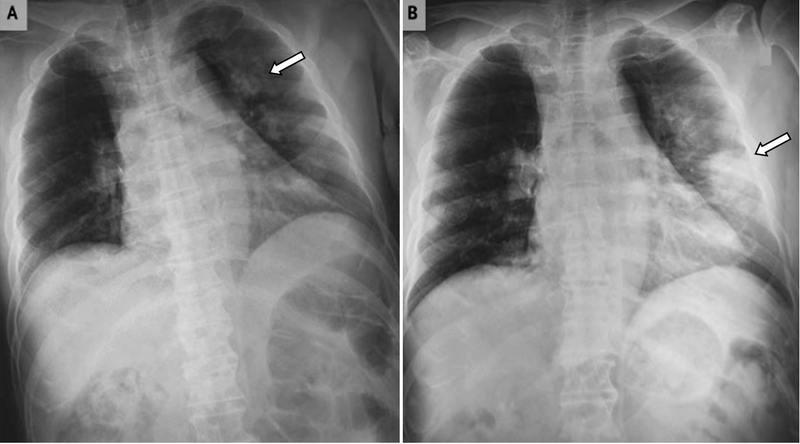

Những điều bạn cần biết về xơ phổi sau Covid 1 Hình ảnh xơ phổi sau Covid

Xơ phổi là tình trạng các mô trong phổi bị tổn thương, mất tình đàn hồi trở nên dày và cứng gây ra sẹo ở phổi. Các mô sẹo này cản trở quá trình hít thở của bệnh nhân và làm giảm chức năng trao đổi khí trong phổi.

Xơ phổi hậu COVID (hay còn gọi là bệnh phổi kẽ hậu COVID) là xơ phổi thứ phát. Đây là tình trạng nhu mô phổi bị phá hủy trong giai đoạn cấp tính sẽ không thể phục hồi trạng thái nhu mô phổi bình thường, mà thay bằng những mô xơ.